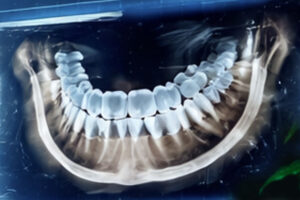

Especialidad: Diagnóstico por Imágenes

Diagnóstico por imágenes en el paciente pediátrico: lo que todo odontólogo necesita saber

Capacitación integral en Tomografía Volumétrica en Odontología

Generalidades de las Tomografía Volumétrica de Haz Cónico (Cone Beam)